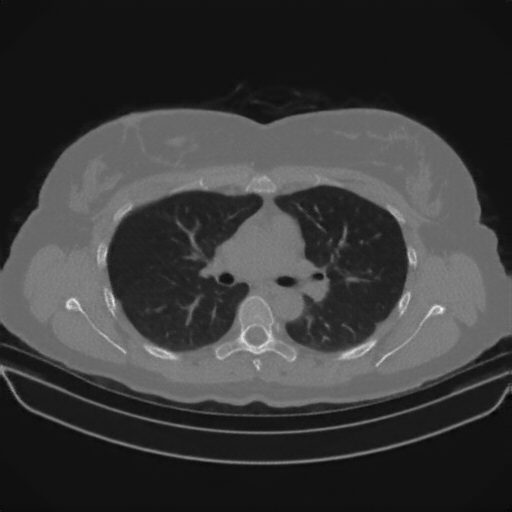

Generated VENOUS CT scan (A→B translation)

No window - Raw intensity values

Lung window (WL -600, WW 1500 β†’ Low βˆ’1350, High +150)

Mediastinum window (WL 40, WW 400 β†’ Low βˆ’160, High +240)